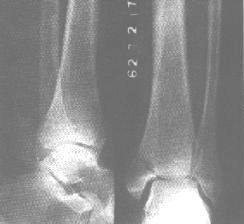

(l)腓骨外踝斜行骨折,遠折端向後移位,骨折向前成角,此種徵象是踝關節外鏇損傷的特徵。以側位片顯示為好。

(2)脛骨內踝骨折,骨折線多為橫行,骨折塊向腓側移位。

(3)脛骨後踝骨折。